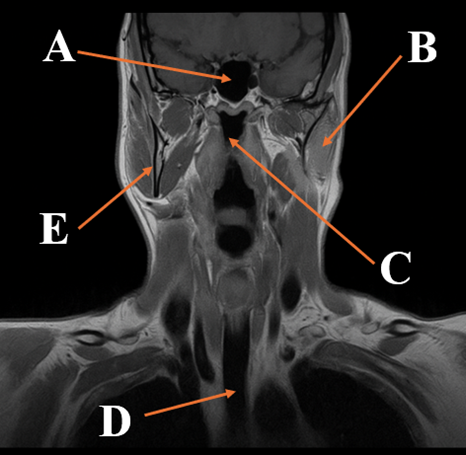

- High-resolution labeled MRI images for anatomy and pathology review

Exclusive Labeled Images

Clear, professional anatomy and pathology images you won’t find elsewhere

- Spine MRI: Cervical, thoracic, lumbar, sacrum and coccyx anatomy, trauma, degenerative disease, tumors, infection